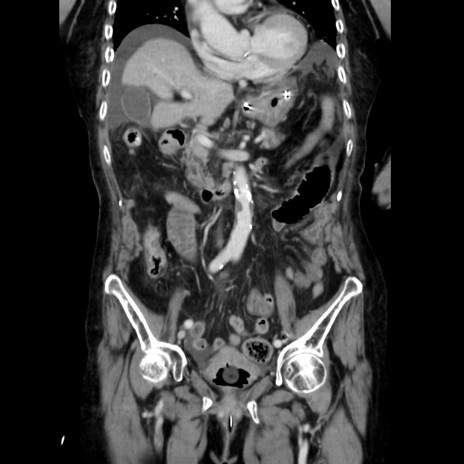

症例40(冠状断像)

冠状断像